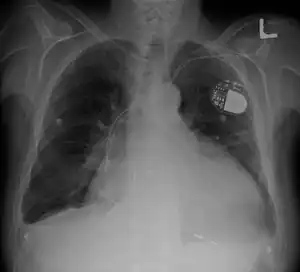

| Cardiomegaly on chest X-ray with a pacemaker | |

- Chest X-Ray: X-ray images help see the condition of the lungs and heart. If the heart is enlarged on an X-ray, other tests will usually be needed to find the cause. A useful measurement on X-ray is the cardio-thoracic ratio, which is the transverse diameter of the heart, compared with that of the thoracic cage."[24] These diameters are taken from PA chest x-rays using the widest point of the chest and measuring as far as the lung pleura, not the lateral skin margins. If the cardiac thoracic ratio is greater than 50%, pathology is suspected, assuming the x-ray has been taken correctly.[25] The measurement was first proposed in 1919 to screen military recruits. A newer approach to using these x-rays for evaluating heart health takes the ratio of heart area to chest area and has been called the two-dimensional cardiothoracic ratio.[26]

- Pacemaker: Coordinates the contractions between the left and right ventricle. In people who may be at risk of serious arrhythmias, drug therapy or an implantable cardioverter-defibrillator (ICD) may be used.